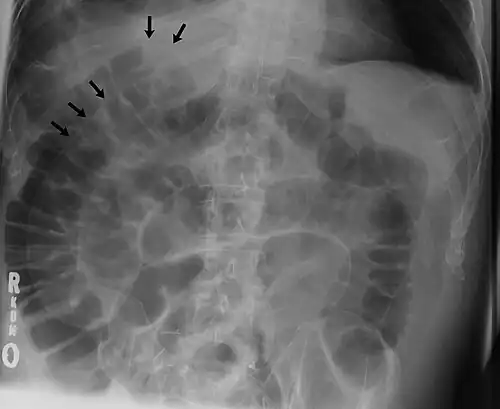

Signs that can be seen on projectional radiography are shown below:

The double wall sign marks the presence of air on both sides of the intestine.[19] However, a false double wall sign can result from two loops of bowel being in contact with one another.[20] The sign is named after Leo George Rigler.[21] It is not the same as Rigler's triad.

Double wall sign. This is a secondary sign of pneumoperitoneum. Patient is supine, and air within the abdomen and lumen of the bowel accentuate both sides of the bowel wall. -